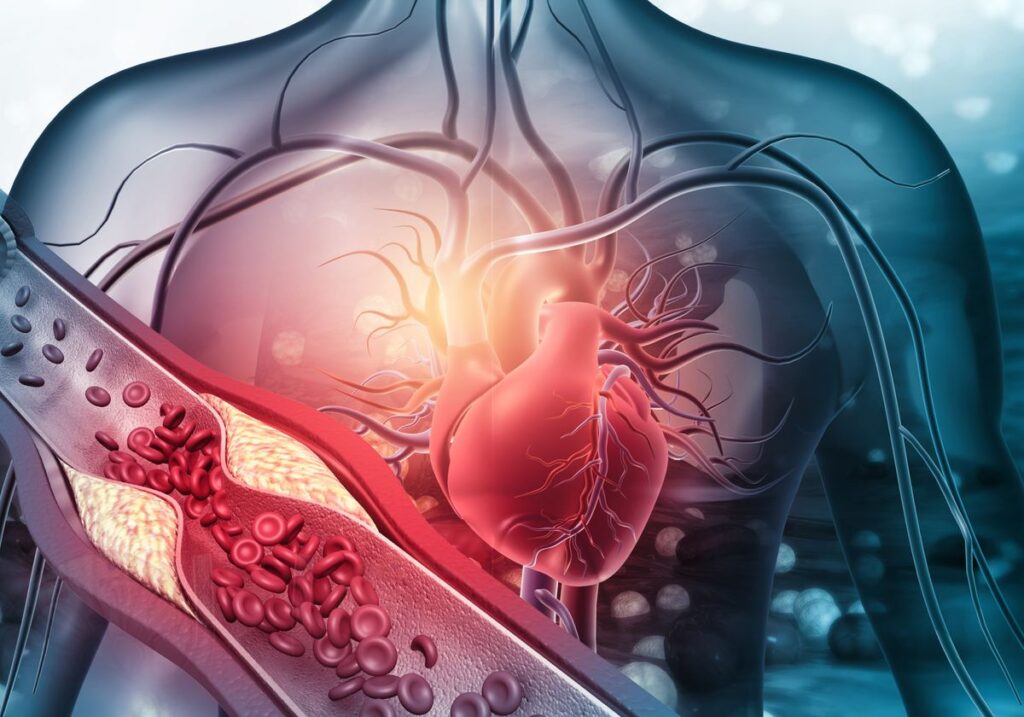

High Lipoprotein(a) levels present a significant risk factor for cardiovascular diseases, and the urgency to address this issue is more pronounced than ever. Surprising statistics reveal that nearly 1 in 5 individuals may have elevated levels of Lipoprotein(a), yet only a fraction has been tested. Understanding and managing Lipoprotein(a) levels could be the key to mitigating severe cardiovascular events such as heart attacks and strokes. In this article, we delve into the critical importance of monitoring Lipoprotein(a) levels and how proactive measures can significantly impact heart health.

Elevated Lipoprotein(a) levels play a pivotal role in the development of arterial plaque. This process leads to a higher risk of cardiovascular events, including heart disease and strokes. As discussed by Katherine Wilemon, founder of the Family Heart Foundation, the presence of high Lipoprotein(a) is linked to the accumulation of cholesterol in the arteries which gradually obstructs blood flow.

Moreover, studies show that those with high Lipoprotein(a) levels, exceeding 300 nmol/L, face a 40% increased likelihood of experiencing cardiovascular events compared to individuals with lower levels. Unfortunately, conventional blood tests often overlook Lipoprotein(a) screening, leaving many at risk without their knowledge.